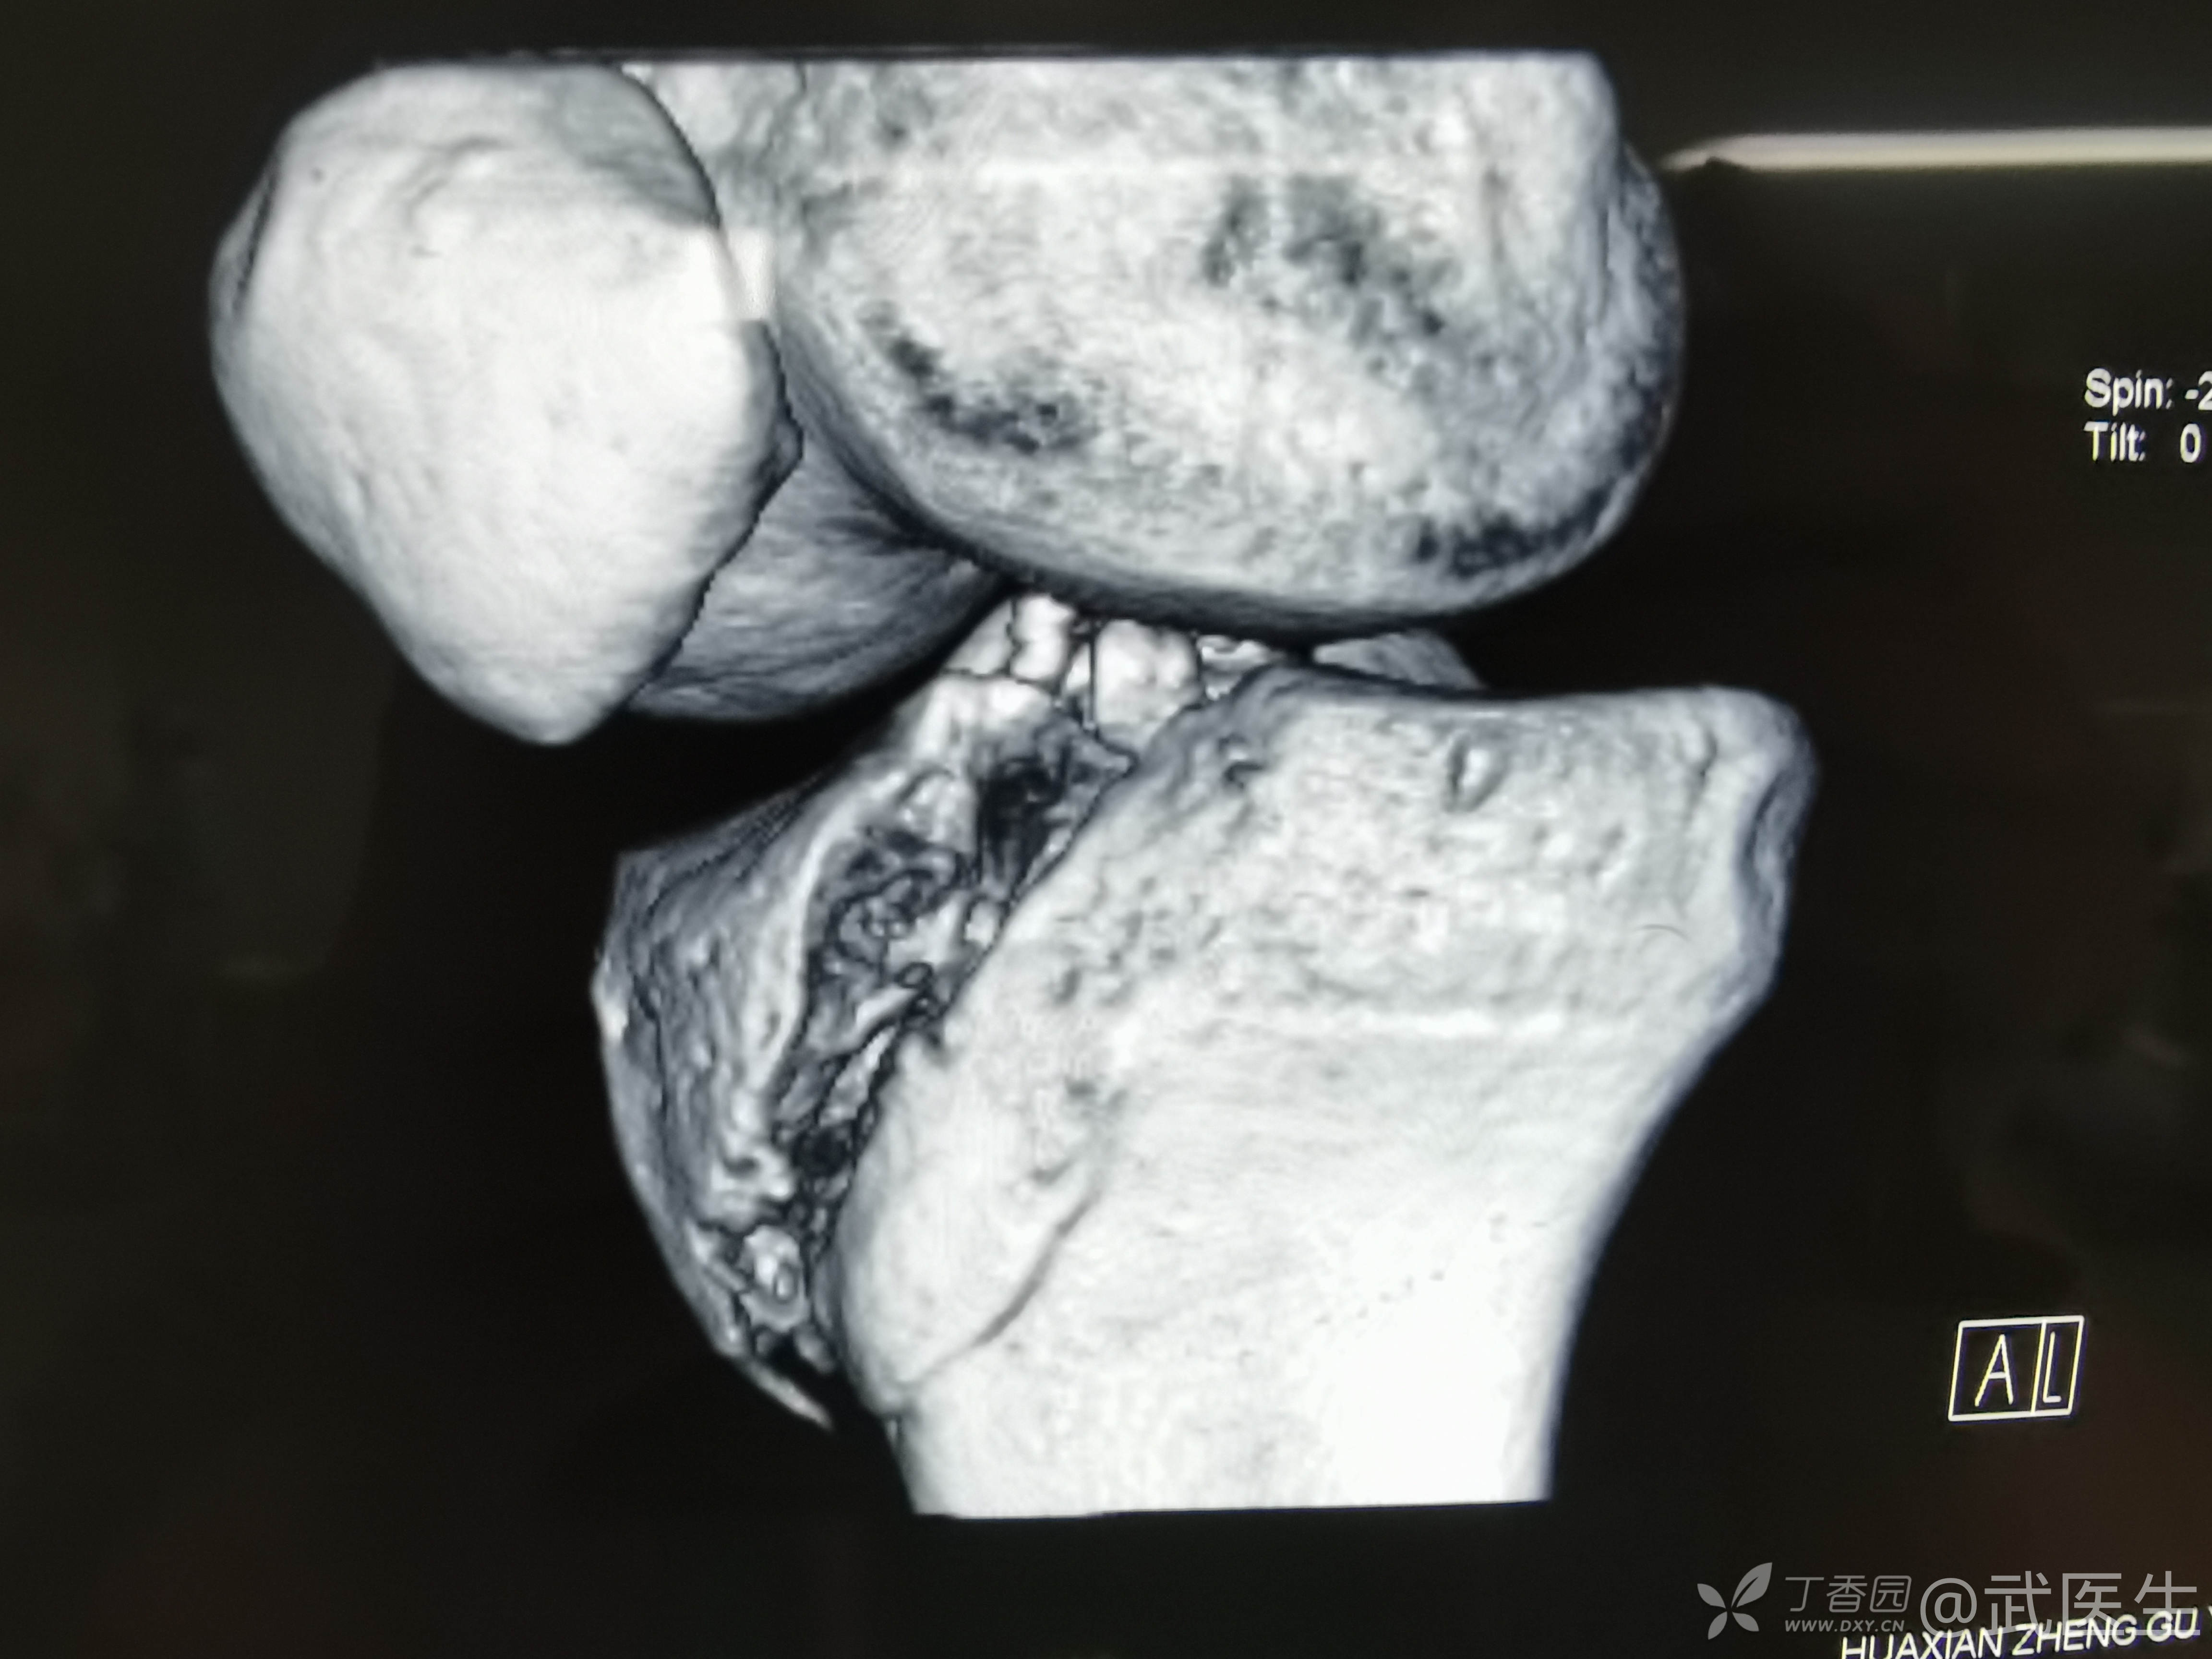

男,15岁,骑摩托车摔伤致右膝疼痛,出血,活动受限三小时就诊,门诊诊断“右胫骨平台骨折,右膝挫裂伤”急诊入院,片子如下,受伤体位照缺失

15岁,骨骺存在,关节加压固定,外侧板支撑